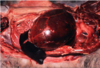

Common name for this disease

“Mulberry Heart Disease”

“Mulberry Heart Disease”